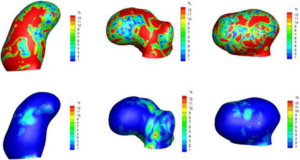

Accuracy of Open-Source Software Segmentation and Paper-based Printed Three-Dimensional Models

Publication: J Craniomaxillofac Surg. 2016 Feb;44(2):202-9. PMID: 26748414 Authors: Szymor P, Kozakiewicz M, Olszewski R. Institution: Department of Maxillofacial Surgery, Medical University of Lodz, Lodz, Poland. Background/Purpose: In this study, we aimed to verify the accuracy of models created with the help of open-source 3D Slicer 3.6.3 software (Surgical Planning Lab, Harvard Medical School, Harvard University, Boston, MA, USA) and the Mcor Matrix 300 paper-based 3D printer. Our study focused on the accuracy of recreating the walls of the right orbit of a cadaveric skull. Cone beam computed tomography (CBCT) of the skull was performed (0.25-mm pixel size, 0.5-mm slice thickness). Acquired DICOM data were imported into 3D Slicer 3.6.3 software, where segmentation was performed. A virtual model was created and saved as an .STL file and imported into Netfabb Studio professional 4.9.5 software. Three different virtual models were created by cutting the original file along three different planes (coronal, sagittal, and axial). All models were printed with a Selective Deposition Lamination Technology Matrix 300 3D printer using 80 gsm A4 paper. The models were printed so that their cutting plane was parallel to the paper sheets creating the model. Each model (coronal, sagittal, and axial) consisted of three separate parts (∼200 sheets of paper each) that were glued together to form a final model. The skull and created models were scanned with a three-dimensional (3D) optical scanner (Breuckmann smart SCAN) and were saved as .STL files. Comparisons of the orbital walls of the skull, the virtual model, and each of the three paper models were carried out with GOM Inspect 7.5SR1 software. Deviations measured between the models analysed were presented in the form of a colour-labelled map and covered with an evenly distributed network of points automatically generated by the software. An average of 804.43 ± 19.39 points for each measurement was created. Differences measured in each point were exported as a .csv file. The results were statistically analysed using Statistica 10, with statistical significance set at p < 0.05. The average number of points created on models for each measurement was 804.43 ± 19.39; however, deviation in some of the generated points could not be calculated, and those points were excluded from further calculations. From 94% to 99% of the measured absolute deviations were <1 mm. The mean absolute deviation between the skull and virtual model was 0.15 ± 0.11 mm, between the virtual and printed models was 0.15 ± 0.12 mm, and between the skull and printed models was 0.24 ± 0.21 mm. Using the optical scanner and specialized inspection software for measurements of accuracy of the created parts is recommended, as it allows one not only to measure 2-dimensional distances between anatomical points but also to perform more clinically suitable comparisons of whole surfaces. However, it requires specialized software and a very accurate scanner in order to be useful. Threshold-based, manually corrected segmentation of orbital walls performed with 3D Slicer software is accurate enough to be used for creating a virtual model of the orbit. The accuracy of the paper-based Mcor Matrix 300 3D printer is comparable to those of other commonly used 3-dimensional printers and allows one to create precise anatomical models for clinical use. The method of dividing the model into smaller parts and sticking them together seems to be quite accurate, although we recommend it only for creating small, solid models with as few parts as possible to minimize shift associated with gluing. |